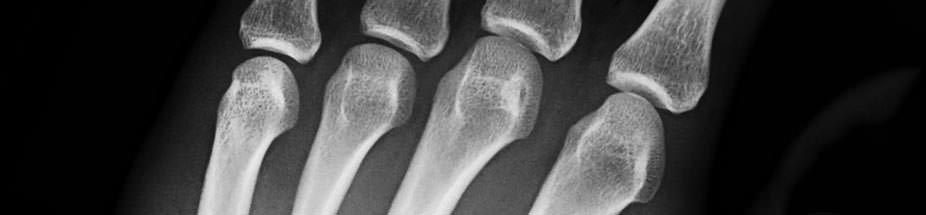

(16.12.2014) Die neu entwickelte Strahlenschutzplatte R48 von MultiGips hat das Potential, die Planung und den Bau von Strahlenschutzwänden in Kliniken und Arztpraxen nachhaltig zu verändern: Statt der herkömmlichen Bleikaschierung sorgt hier Baryt (Bariumsulfat) als direkter Zusatz zum Wandbildner für die abschirmende Wirkung. Der große Vorteil: Strahlenschutzwände aus massiven Gips-Wandbauplatten nach DIN EN 12859 sind keine Sonderkonstruktionen. Sie werden wie nichttragende Trennwände in der nach DIN 4103-2 geregelten Bauweise geplant und ausgeführt.

Die Untersuchungen beim TÜV NORD ergaben zudem, dass für bestimmte Diagnosegeräte in der Zahnmedizin und der Mammographie der geforderte Strahlenschutz sogar mit Gips-Wandbauplatten ohne Barytanteil erreicht werden kann, was die Wirtschaftlichkeit der Bauweise weiter erhöht.